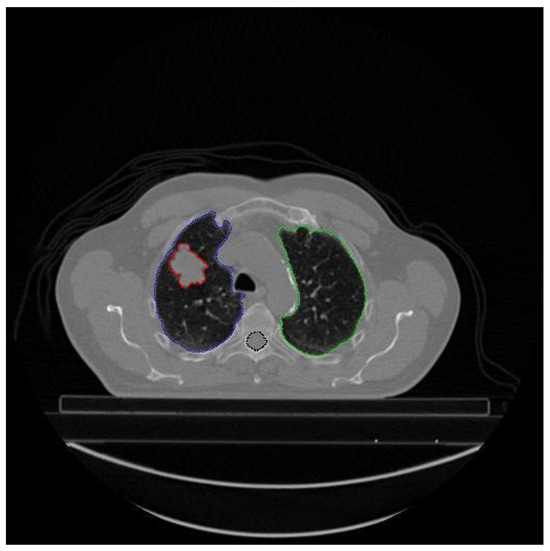

Each patient’s file may contain different types and numbers of segmented images. The type and number of segmented images are not standard. For example the number of CT images (number of slices) taken from patient LUNG1-001 is 134, and there are a total of 358 segmented images labeled 139 Left-Lung, 134 Right-Lung, 84 Spinal-Cord, and 21 GTV-1, while LUNG1 has 94 slices, LUNG1-243 has a total of 327 segmented images, 113 of which are labeled Left-Lung, 101 Right-Lung, 94 Spinal-Cord, 6 GTV-2, and 13 GTV-1. Additionally, different types and/or numbers of segmented image data may be present in different slices of the same patient. For example, different types of segmented data in CT slice number 28 of patient LUNG1-243 are given in Figure 3.

As seen in Figure 3, segmented data with all different labels may not be present in a slice of a patient. This is because, in the axial CT image, each slice represents a scan of a specific region of the lung. In the example above, blue indicates the Lung-Left, green the Lung-Right, red the GTV-1 region, and black the Spinal-Cord. There is no GTV-2 image of the patient in the 28th CT image for LUNG1-243.